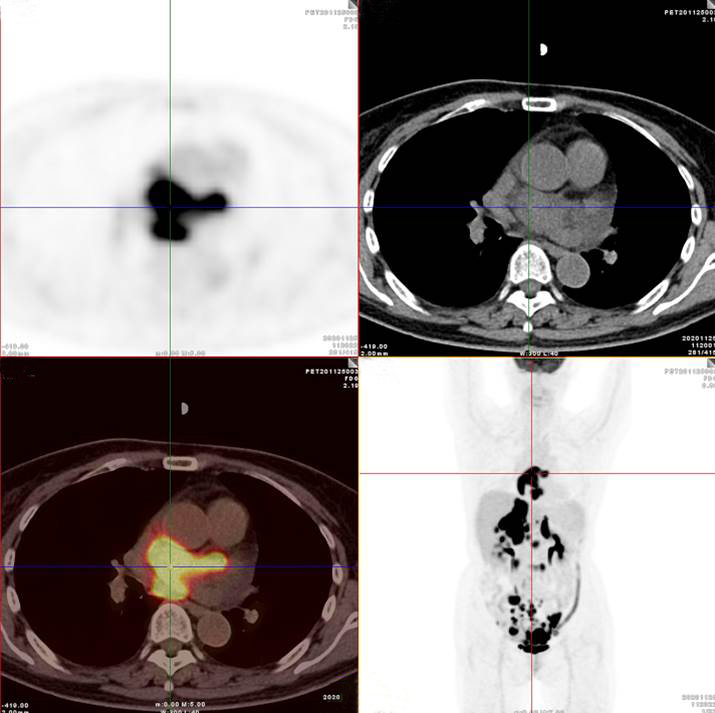

左/右心房病灶放射性攝取明顯增高

左/右心房壁增厚、雙側(cè)腎上腺腫塊、膽囊壁結(jié)節(jié)、胃竇壁結(jié)節(jié)及多段小腸腸壁增厚,上述代謝不同程度明顯增高;腹膜后、腸系膜多發(fā)高代謝淋巴結(jié)。

考慮淋巴瘤,請結(jié)合臨床病理